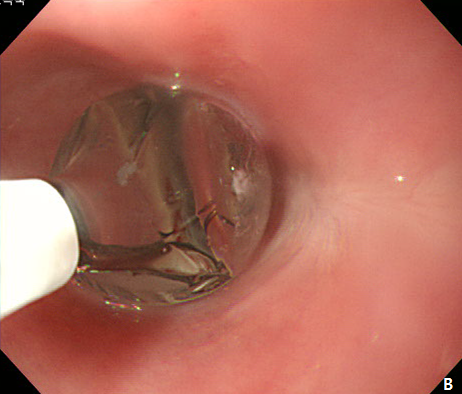

Figure 2 Endoscopic submucosal dissection (ESD) of esophageal subepithelial tumor (SET).

(A) At initial,an incision was made from the regular mucosal layer. (B, C) Esopahgeal SET was successfully resected by using conventional ESD method. (D) A large muocsal defect was noted after the procedure.